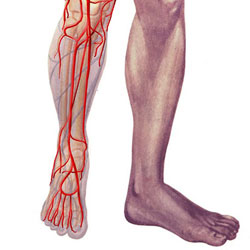

Érelzáródás az alsó végtagok, a kezelést népi jogorvoslat

Olvashatatlanná endarteritis úgynevezett krónikus patológia, amelyben a perifériás erek sérülnek, vagy inkább a kis artériák a lábakban. Ez egy veszélyes betegség okozza a rossz keringés a távolabbi lábát. Egy nő endarteritis számla 99 képviselői az erősebb nem. A jelentősége ennek a betegségnek az oka, hogy a fogyatékosság alapján történő elvesztése miatt végtag (amputáció) a fiatalabb, munkaképes korú népesség.

Nem keverendő érelzáródások az alsó végtagok atherosclerosis obliterans - annak ellenére, hogy mindkét betegség hasonló tüneteket, etiológiája és patogenezise közülük egészen más. Elzáródásos betegség fordul elő az emberek 20 és 40 év, és hatással van a láb és a lábszár artériák. Atherosclerosis van jelölve az idősek és befolyásolja elsősorban a nagy ereket, tartózkodási helytől függetlenül.

Klinikailag elzáródásos betegség az alsó végtagok nyilvánul meg a megjelenése időszakos sántítás és súlyos fájdalom az érintett területen.